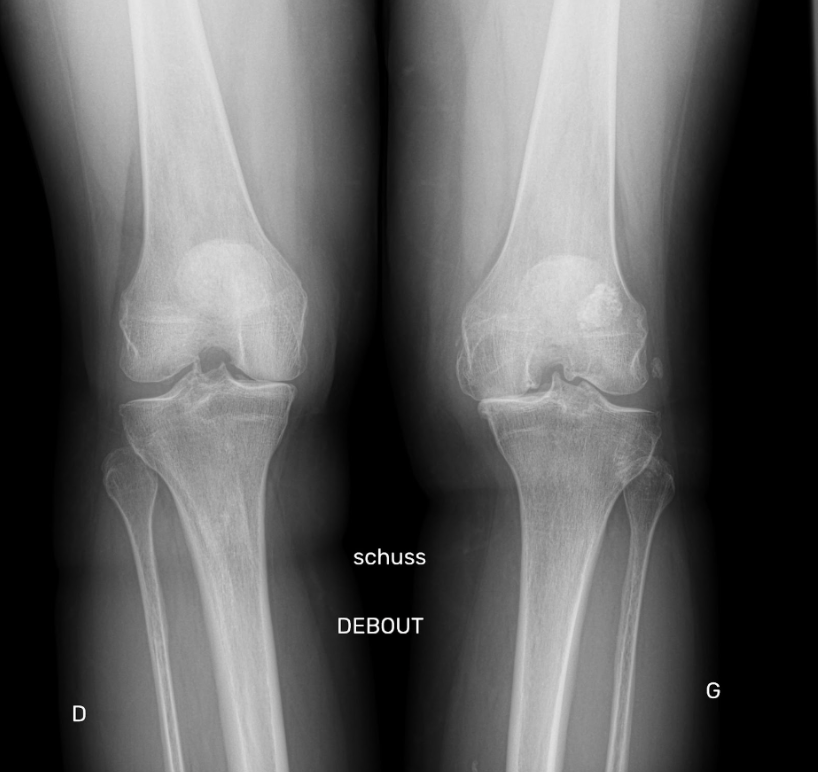

Le diagnostic de l’arthrose du genou se fait par l’évaluation des symptômes, des antécédents médicaux et des examens radiologiques tels que les radiographies. En cas de progression de la maladie et de douleurs persistantes malgré les traitements non chirurgicaux, une prothèse totale du genou peut être envisagée.

Le diagnostic de l’arthrose du genou est établi en fonction des symptômes, des antécédents médicaux et des radiographies pour évaluer l’état des surfaces articulaires et des os du genou.

La chirurgie devient la seule solution lorsque le traitement médical n’est plus efficace et que les examens complémentaires (radiographies) mettent en évidence une arthrose avancée. Ce traitement chirurgical est le remplacement de l’articulation par une prothèse du genou.